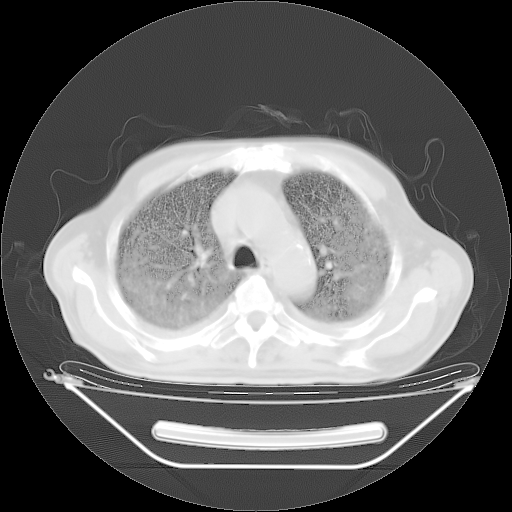

今天复查肺部CT,发现双肺广泛磨玻璃样改变。所以我把3月19日和5月9日相隔50天的肺部CT上传。请大家会诊。

2009年3月19日肺部CT片。

5月9日肺部CT(在4月27日齐鲁医院肺部CT描述部分肺组织磨玻璃样改变,12天后肺组织广泛磨玻璃样改变)

大致读了系列胸部CT:纵隔窗无明显异常,肺窗:从4、27至今:主要是双肺中下野外带可见毛玻璃样改变,目前处于急性肺泡炎阶段,至于原因考虑1、结替组织或胶原血管性疾病所致?2、恶性疾病如恶组在肺部所致的表现或细支气管肺泡癌?3、药物或其它原因如肺蛋白沉着症所致肺泡炎目前不太可能?总之,明天就去请我院的呼吸科、感染科、血液科和临免专家会诊哈。